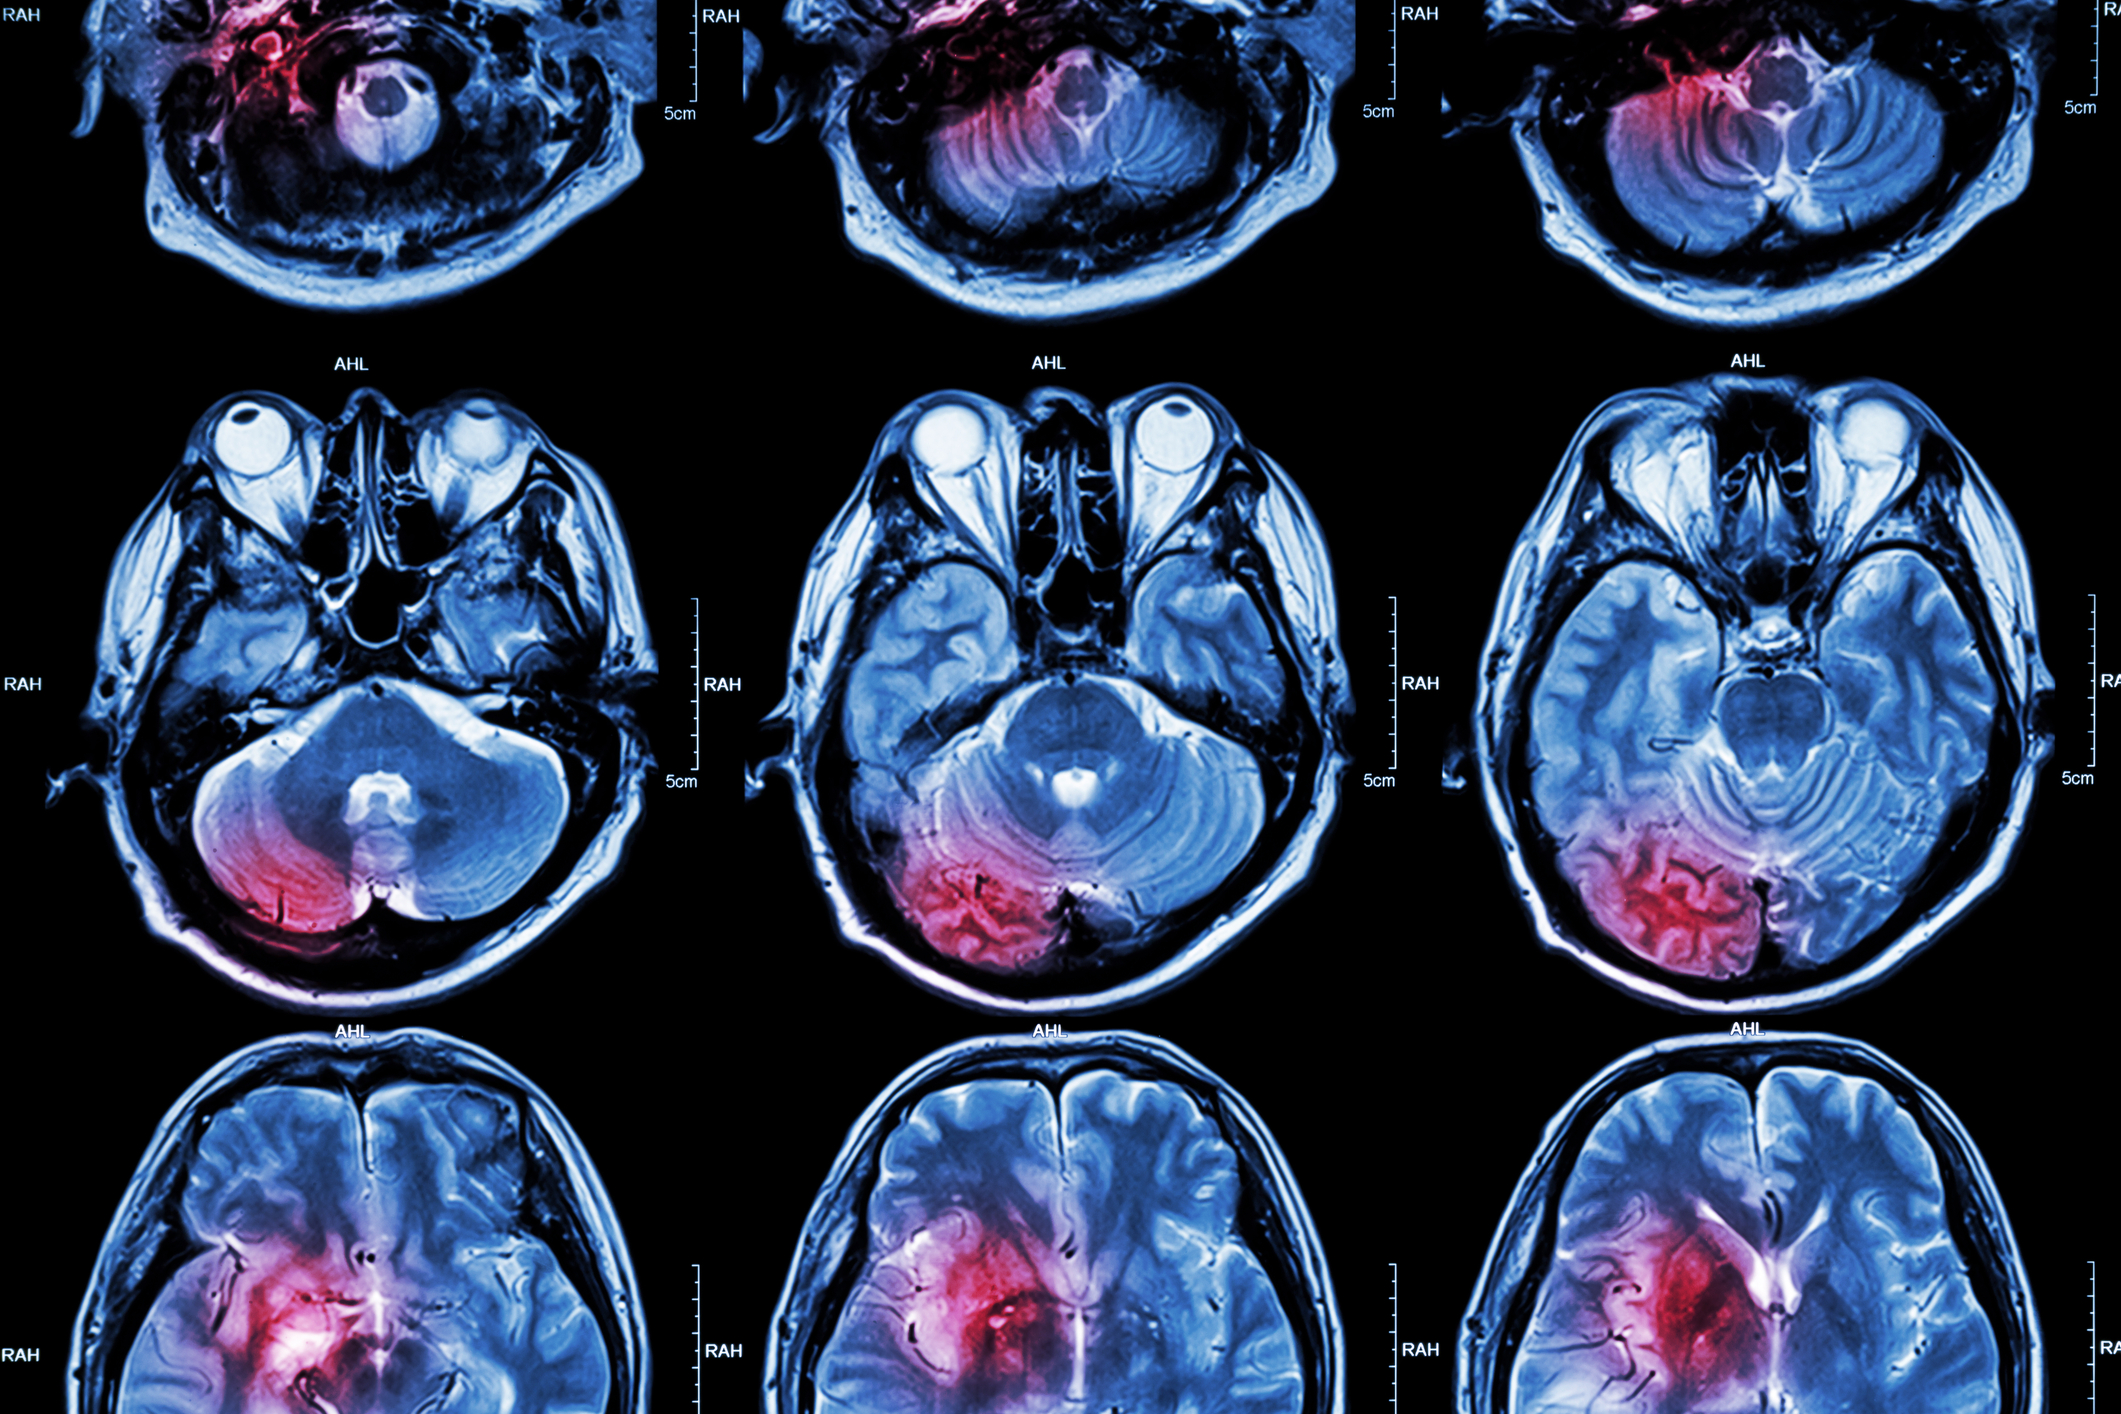

Magnetic resonance imaging (MRI) revolutionized medical diagnostics by evolving from nuclear magnetic resonance discoveries to life-saving technology.

Magnetic Resonance Spectroscopy (MRS), a variant of conventional Magnetic Resonance Imaging (MRI), is an advanced diagnostic technique that offers a unique glimpse into the molecular composition of tissues. Unlike standard MRI, which provides detailed images of anatomical structures, MRS focuses on the chemical contents of cells, making it a crucial tool in medical diagnostics and research.

This technique operates on the principle of nuclear magnetic resonance, detecting the presence and concentrations of various metabolites within the body. By analyzing these chemical signatures, MRS can identify subtle biochemical changes that often precede visible pathological alterations. This capability makes it particularly valuable for early diagnosis and for monitoring the progression of diseases, including cancer, neurological disorders, and metabolic dysfunctions.

One of the primary applications of spectroscopy MRI is in the field of neurology, where it is used to evaluate brain tumours, epilepsy, and degenerative diseases like Alzheimer’s and Parkinson’s. By measuring the levels of specific brain chemicals, such as N-acetylaspartate, choline, and creatine, clinicians can gain insights into cell density and brain metabolism, aiding in the assessment of disease severity and the response to therapy.